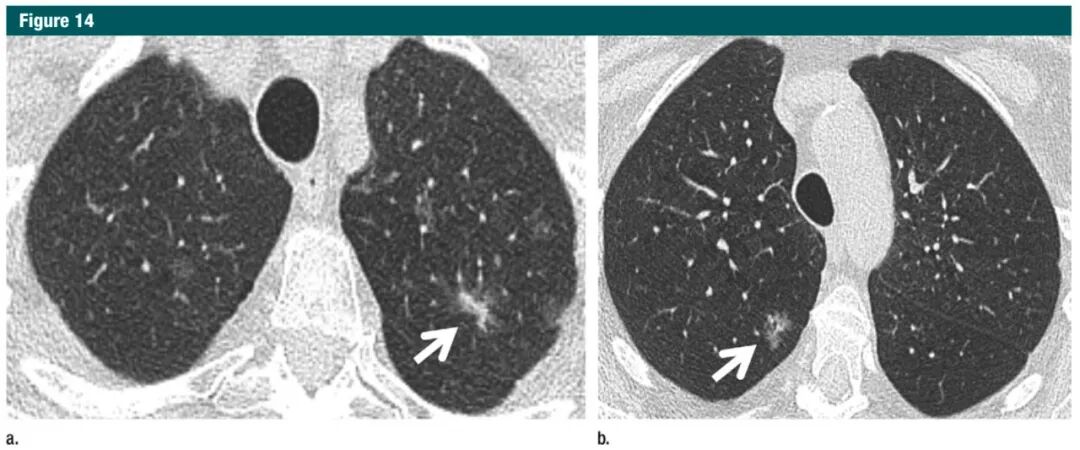

在多发亚实性结节病灶中,且至少有一个≥6mm 的结节,处理方案应该基于最可疑的结节而定。在这些病例中,要考虑到感染因素。如果 3-6 个月后仍然存在,要考虑多原发性腺癌(级别 1C)。多发亚实性结节,且≥6mm的患者,应以最可疑病灶(未必是最大的病灶)来决定处理方案(图14)。但是,涉及主要结节的介入和手术的决定必须谨慎,因为其他存在的结节有潜在增大和需要治疗的可能。同时,多个可疑结节与孤立性结节相比,总体的癌变可能性更大。

图片7Gc帝国网站管理系统

图14:a.横断位1mmCT,上叶层面,显示两肺多发大小不一的亚实性结节,包括至少一个位于左上肺的高度可疑部分实性结节(结节大,磨玻璃样和实性形态),首次随访以3-6月为宜;b.同一次检查显示右肺上另一个高度可疑的结节(分叶状、10mm左右磨玻璃样),这个结节同样需随访;这些结节最符合多原发性腺癌。7Gc帝国网站管理系统